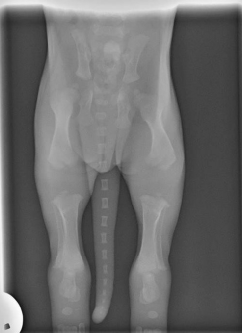

Below is an x-ray of a puppy at 2 weeks old. Just look to see how far the bones have to grow to just become proper bony joints that have correct feedback to the brain……this is why it is imperative that we don’t over exercise our puppies, and certainly not jump them or train them too hard before they are fully developed. This is a different age categories for different breeds, and if the dog has had any specific problems during its puppy hood. Please be careful at this stage so the dogs joints will last as well as they age! Longevity is the key.